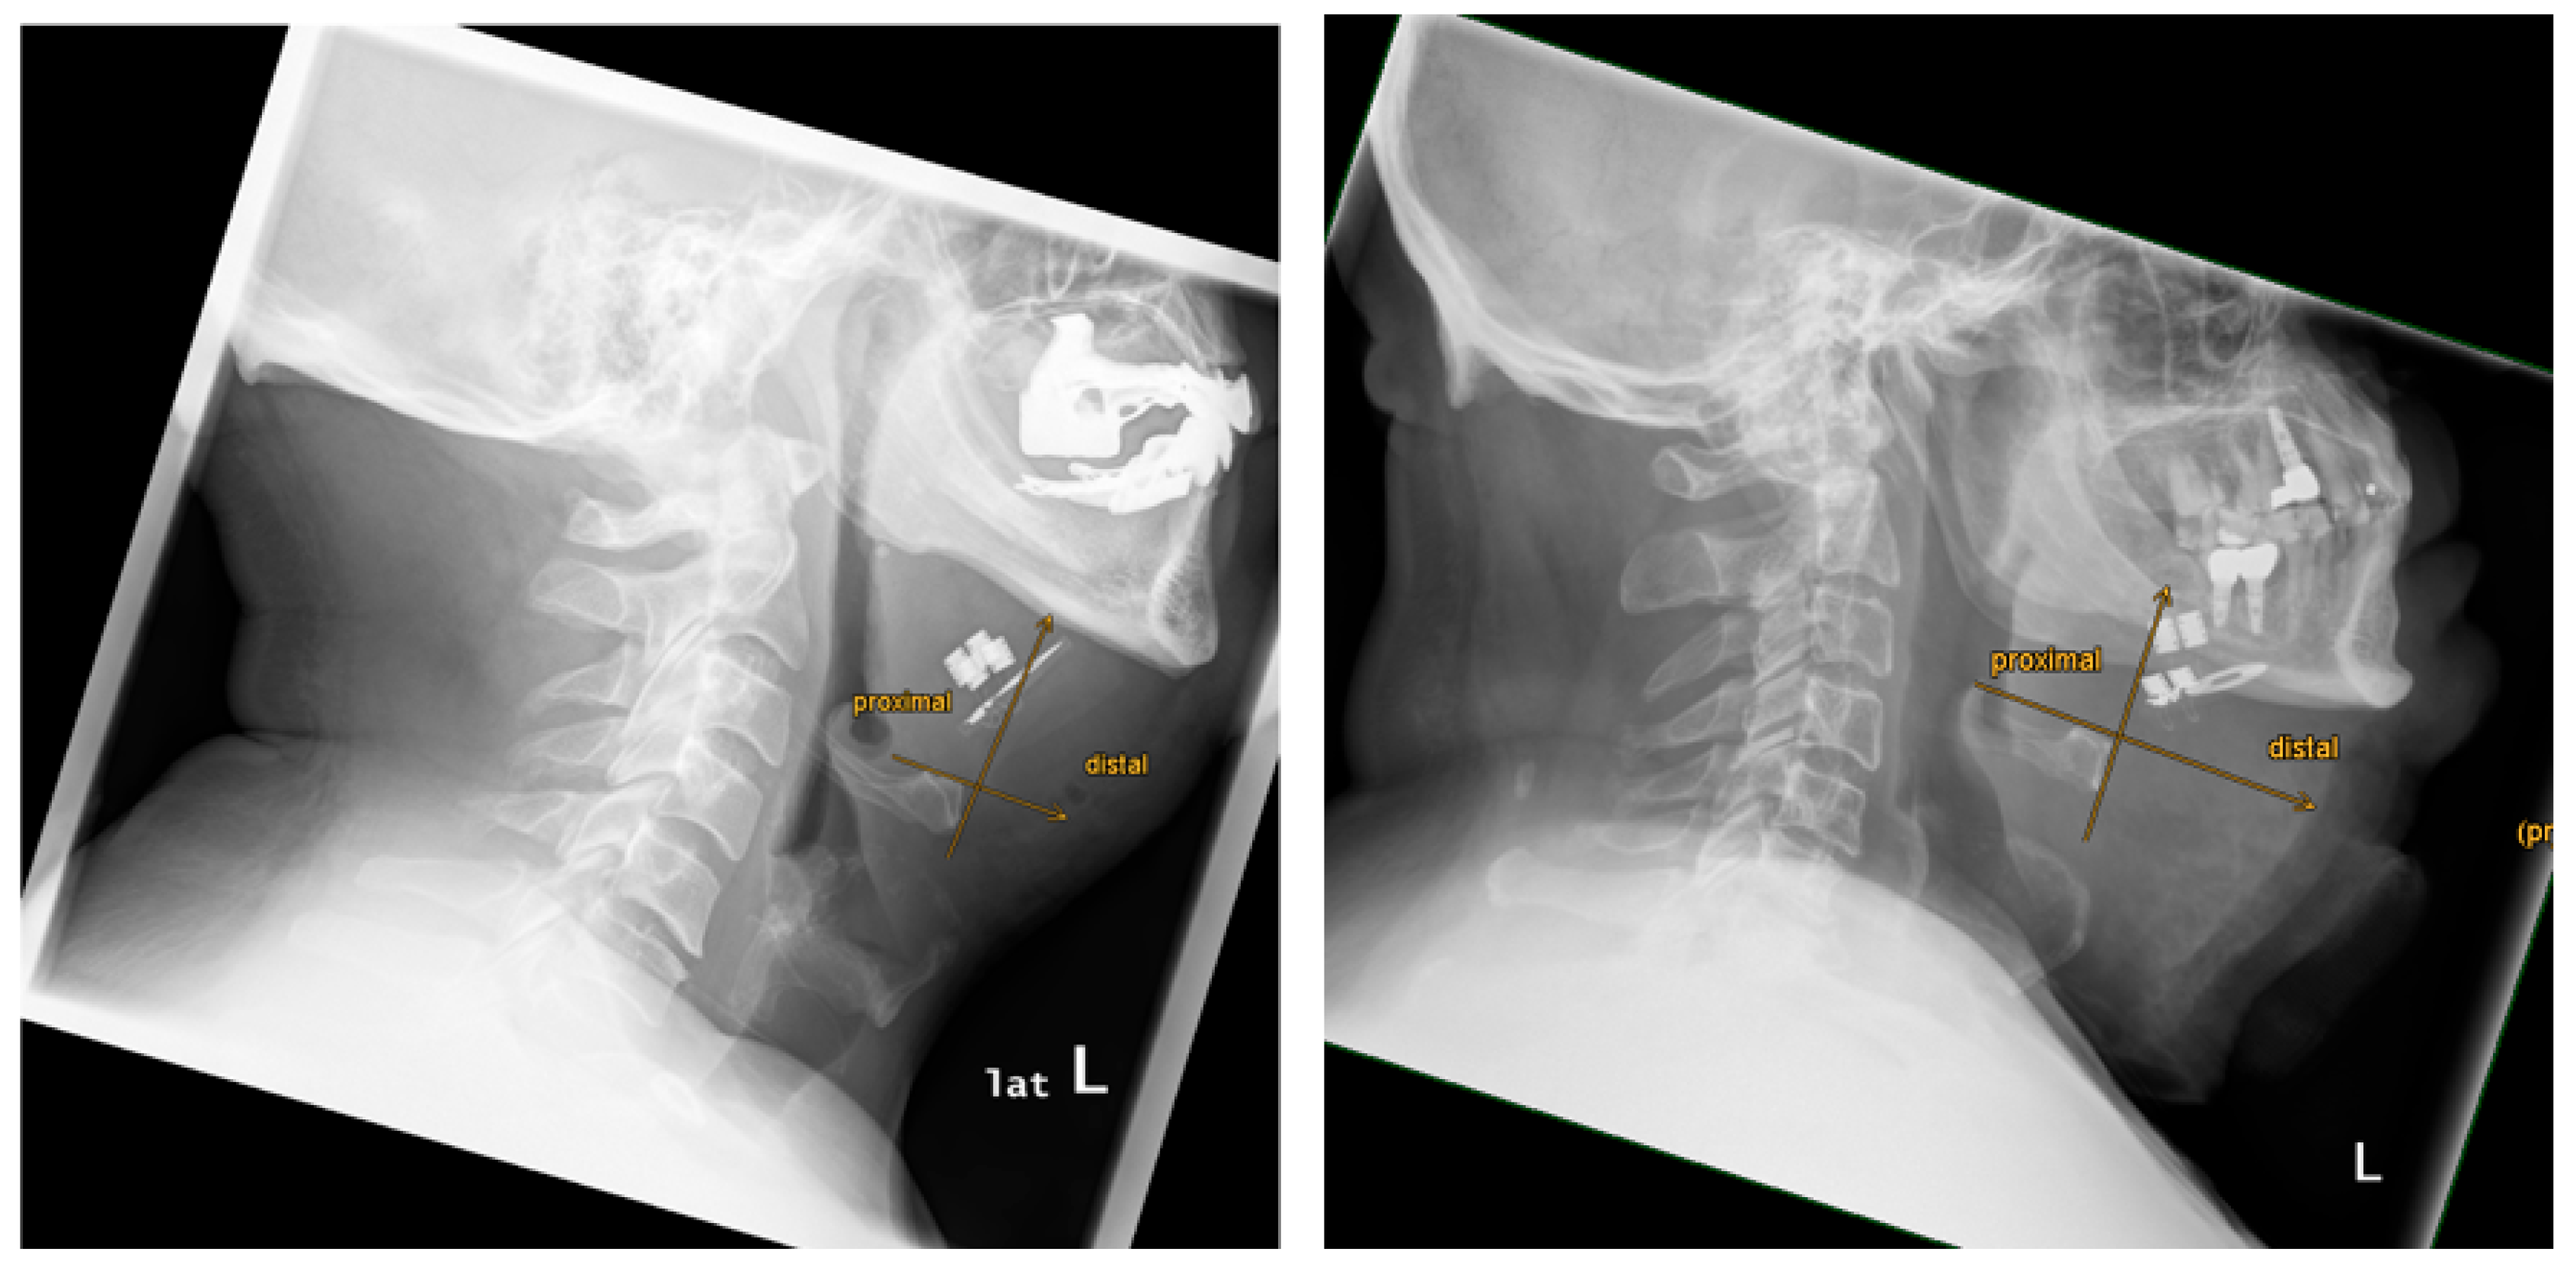

| 1 | 33 | 26 | yes | yes | yes | moderate | no | yes | 87,3 | 28,7 | 56,4 | 15,2 | 7,9 | 22,6 | -14,7 | asymmetry | 64,9 | proximal | proximal |

| 2 | 47 | 30 | yes | yes | yes | strong | no | yes | 94,1 | 45,7 | 57,0 | 19,0 | 18,7 | 19,3 | -0,6 | symmetry | 70,4 | proximal | proximal |

| 3 | 51 | 28 | yes | no | n/a | n/a | no | yes | 109,3 | 32,6 | 48,4 | 17,2 | 15,0 | 19,3 | -4,3 | asymmetry | 60,3 | proximal | proximal |

| 4 | 64 | 31 | yes | yes | yes | moderate | no | yes | 113,9 | 55,3 | 76,2 | 25,9 | 18,8 | 32,9 | -14,1 | asymmetry | 73,8 | proximal | proximal |

| 5 | 37 | 32 | yes | yes | yes | strong | no | yes | 93,2 | 23,9 | 54,5 | 15,4 | 13,9 | 16,9 | -3,0 | asymmetry | 35,3 | proximal | proximal |

| 6 | 52 | 25 | yes | yes | yes | moderate | no | yes | 86,0 | 20,3 | 47,1 | 15,8 | 15,6 | 16,0 | -0,4 | symmetry | 19,0 | proximal | distal |

| 7 | 28 | 28 | yes | yes | yes | moderate | no | yes | 102,0 | 36,7 | 64,3 | 16,4 | 14,4 | 18,3 | -3,8 | asymmetry | 40,7 | proximal | distal |

| 8 | 16,5 | 34 | yes | yes | yes | strong | no | yes | 122,3 | 32,1 | 77,9 | 12,5 | 18,4 | 6,6 | 11,8 | asymmetry | 39,9 | proximal | distal |

| 9 | 32 | 29 | yes | yes | yes | moderate | no | yes | 110,5 | 40,3 | 69,4 | 16,6 | 14,9 | 18,2 | -3,2 | asymmetry | 63,5 | proximal | proximal |